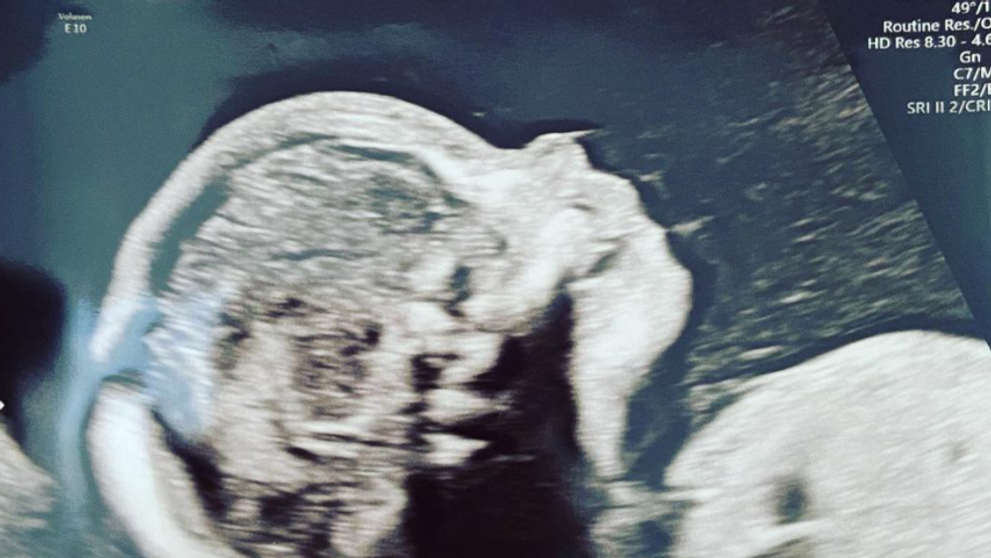

Herečka, ktorej prelomová rola bola postava Wednesday vo filme Rodina Addamsovcov, zverejnila záber z ultrazvuku, ku ktorému napísala: „Život sa stále zlepšuje“.

Christinin priateľ Mark Hampton, ktorý je vlasový štylista, takisto zverejnil fotku z ultrazvuku s rovnakým popisom.

zdroj: Instagram/riccigrams